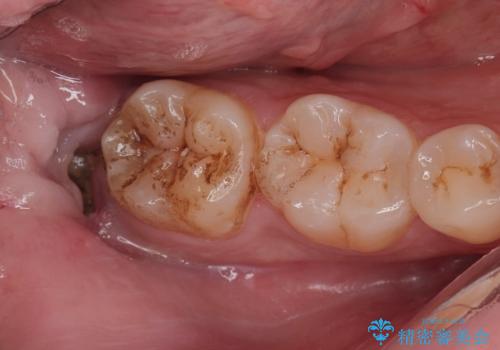

親知らず抜歯後、虫歯治療

- 親知らずが痛くて抜いて欲しいとの事で来院。CTで神経の位置を確認し、抜歯を行いました。

抜歯後、奥歯にも虫歯があったので虫歯を拡大鏡下で取りきり、メタルインレーにて治療を行いました。

しっかり麻酔を効いてるのを確認し治療を行いました。